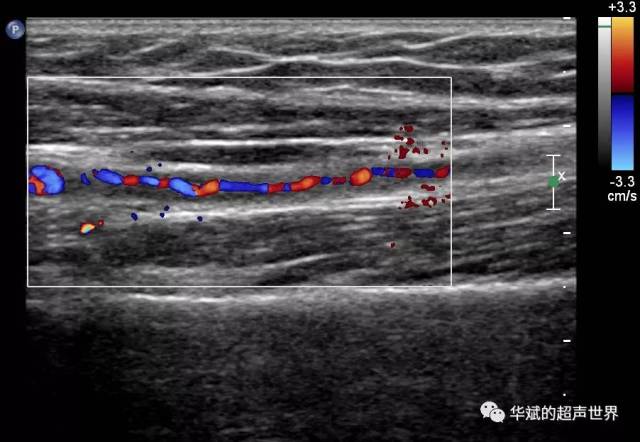

超声检查将双侧小腿动脉管腔不清,管腔内为红蓝相间的详细血流信号.

胫前动脉血栓,侧支循环形成 - 超声医学讨论版 - 爱爱